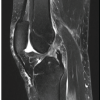

A 46-year-old woman presented to the emergency room with the right knee pain and swelling which had worsened over the past 2 weeks. The patient was unable to fully extend her knee secondary to pain and restriction from swelling. Radiographs were obtained and showed no osseous lesions or fractures. Blood work was obtained which revealed a white blood cell count of 12.7, C-reactive protein of 7.2, and erythrocyte sedimentation rate of 105. The patient was evaluated by the internal medicine service and orthopedics was consulted to rule out septic right knee. A right knee aspiration was performed which revealed a synovial white blood cell count of 6500, polymorphonuclear leukocytes of 71%, and no crystals present. The patient was admitted for further evaluation and vancomycin was prophylactically started to treat suspected infections due to her worsening symptoms. On hospital day 2, a new fluctuant area with erythema and tenderness was identified on her medial proximal tibia. Magnetic resonance imaging with and without contrast was obtained of her right lower leg (Fig. 1) which revealed a complex Baker’s cyst and observation recommended due to aspiration results not concerning for septic arthritis. The following day, the patient developed a fever, worsening anion-gap metabolic-acidosis and became tachycardic and disoriented. An aspiration was performed of the posteromedial knee fluid collection which revealed purulent aspirate. Subsequently, as a results of the aspiration findings, an incision and debridement were performed of dressing. Two hundred milliliters of purulent fluid were evacuated and multiple cultures were sent for analysis. After the Baker’s cyst decompression, the flexion contracture resolved. Cultures from the Baker’s cyst aspiration and intraoperative cultures grew pansensitive Methicillin-Sensitive Staphylococcus aureus (MSSA).